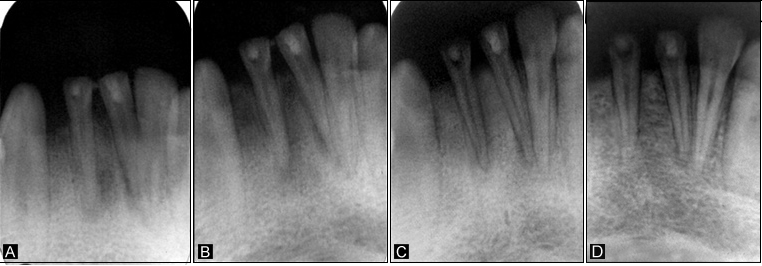

A twelve-year-old male patient reported to the Department of Pedodontics and Preventive Dentistry, complaining of fractured lower anterior teeth. The patient gave a history of trauma six months back and on clinical examination, an Ellis class IV fracture was seen in teeth #31 and #41. Radiographic examination revealed periapical radiolucency involving both #31 and #41 (Figure 4a). The teeth tested negative to both electric and heat tests. After obtaining parental consent, it was decided to complete the access (Figure 3a) and biomechanical preparation in the first visit, followed by 3Mix (1:1:1 ratio) placement and closure of the access cavity with zinc oxide-eugenol cement. During subsequent appointment after two days, the canals were thoroughly irrigated with normal saline, followed by drying with paper points and placement of tissue scaffold PerioGlas® (bioglass) and homing of SHED from apex to 5 mm of the access cavity with a 25-gauge needle in the root canals of teeth #31 and #41 (Figure 3b). A 5-mm thickness of glass-inomer cement was used to seal the access cavity. The patient was scheduled for recall examination and advised to call if he felt pain. On recall examination after one week, the patient was asymptomatic and reported no pain (Figure 4b). In the 30-day review, the patient was asymptomatic and had no signs of pain or tenderness upon vertical percussion. The radiograph showed significant resolution of radiolucency in relation to teeth #31 and #41 from 30-day recall to the 365-day follow-up (Figure 4c and 4d) and responded positively to electric pulp testing from the 90-day to 365-day recall evaluation. The improvement in the radiolucency may be due to the healing capability of SHED placed in the sterile cavities of teeth #31 and #41. Upon reaching the apical area, SHED might have proliferated and transformed to osteoblast-like cells, leading to bone formation.

Figure 3.a. Preoperative image after access opening; b. Homing of stem cells in #31 and #41.

Figure 4.A: Periapical radiolucency in relation to teeth #31 and #41; B: 7-day post-operative radiograph; C: 30-day follow-up radiograph showing complete resolution of radiolucency in relation to teeth #31 and #41; D: 12-month review radiograph.